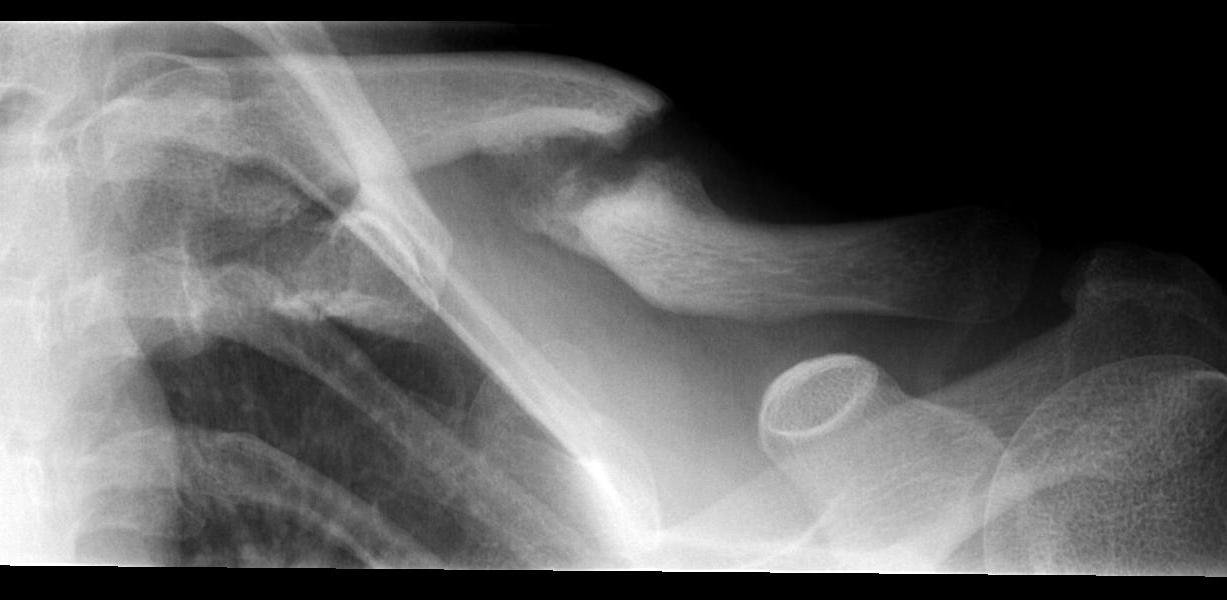

Compound clavicle fracture

Shorted / displaced midshaft clavicle fractures

Z shaped midshaft clavicle fracture